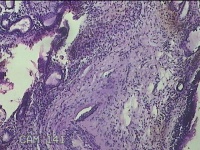

右侧鼻腔新生物

性别

女

年龄

31岁

临床诊断

1.鼻息肉 2.变应性鼻炎

一般病史

反复鼻塞、流涕嗅觉减退1年。

标本名称

大体所见

灰白暗红色不规则碎组织1.5x0.7x0.3cm一块,表面糜烂,内有少许骨质。